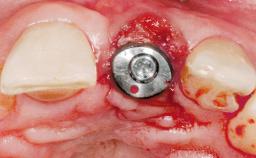

A 30-year-old female patient had lost tooth 21 and was referred to our clinic for consultation and treatment. Due to advanced apical infection, tooth 21 had been extracted two months earlier at another clinic and an acrylic-resin tooth had been bonded to the adjacent teeth. The patient desired implant treatment to avoid any damage to the adjacent natural teeth. While the patient had no history of any systemic disorder, she was a heavy smoker and exhibited medium to advanced periodontitis in the entire jaw. After the initial treatment to achieve a pocket probing depth of less than 4 mm and no bleeding on probing, a decrease in the height of the papillae mesial and distal to the extraction site and overall gingival recession were observed.

Bone Augmentation Horizontal|Staged

Augmentation Materials Autogenous chips|Membrane

Bone Volume Deficient horizontally, requiring prior grafting